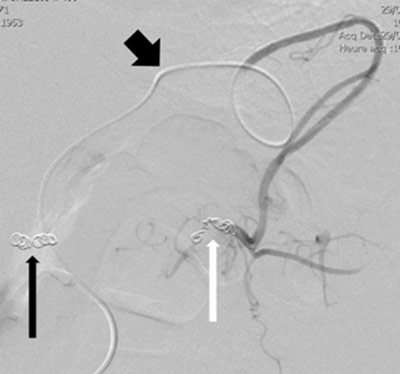

Figure 4b

Microcoils embolization of the distal splenic artery (white arrow) through superselective catheterism of the gastroepiploic arteries (thick black arrow); the thin black arrow indicates the previous ostial coiling.